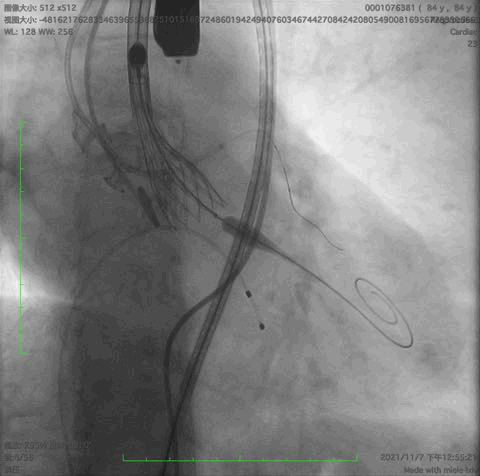

主动脉根部造影,冠脉开口保护

释放到1/3处造影

释放到回收极限造影

瓣膜完全释放后造影,形态良好,无瓣周漏